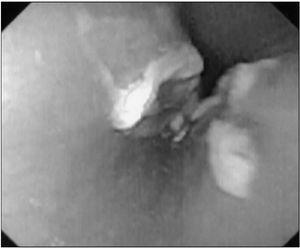

Se efectuó fibroesofagogastroscopia con el hallazgo en la mucosa esofágica del tercio medio de dos lesiones contralaterales de 2 cm de longitud, con base eritematosa y abundante fibrina (kiss-ulcers), el resto de la mucosa no muestra alteraciones (fig. 1). Se instauró tratamiento con sucralfato y omeprazol con mejoría progresiva de los síntomas, y quedó asintomática a partir del cuarto día de tratamiento. Al cabo de un mes se realizó esofagograma, que fue normal.

Figura 1. Imagen de úlceras producidas por doxiciclina (kiss-ulcers).